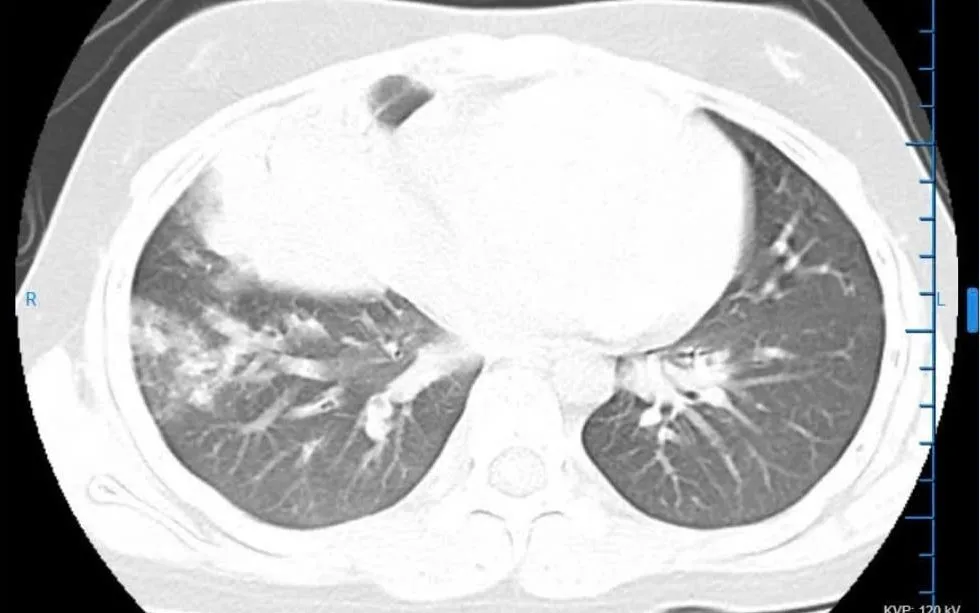

VTV.vn - Bệnh nhi 11 tuổi nhập viện trong tình trạng sốt cao, ho nhiều, đau ngực, được chẩn đoán viêm phổi thùy và điều trị thành công tại Bệnh viện Đa khoa Vân Đình (Hà Nội).

Theo các bác sĩ, bệnh nhi nhập viện trong tình trạng sốt cao liên tục, ho nhiều, đau tức ngực, mệt mỏi, ăn uống kém. Qua thăm khám lâm sàng kết hợp các xét nghiệm cận lâm sàng cần thiết, bệnh nhi được chẩn đoán viêm phổi thùy và chỉ định điều trị tích cực tại Khoa Nhi.